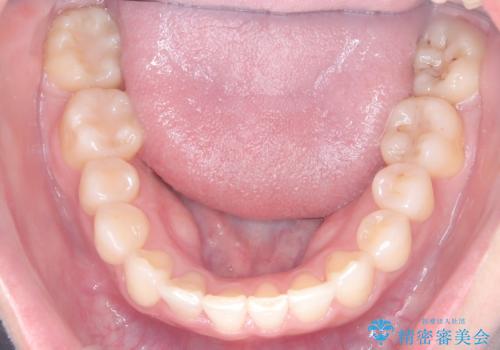

- 患者様は、下顎両側の第1大臼歯(6番)と右上6番の欠損を主訴に来院されました。

通常であればインプラントによる補綴が第一選択となる症例でしたが、患者様ご自身がインプラントを希望されなかったため、矯正治療によって欠損部の閉鎖を図る方針としました。

同時に、親知らず(智歯)の萌出や位置も考慮し、咬合全体のバランスを改善する矯正治療計画を立案しました。

ワイヤー矯正を用いて、欠損部の閉鎖を目的とした後方からの歯の挺出・移動を行いました。

特に、親知らずを活用し、奥歯の噛み合わせを構築することに重点を置きました。

最終的には予定通りインプラントを使用せずに欠損部を閉鎖し、咬合も安定させることができました。